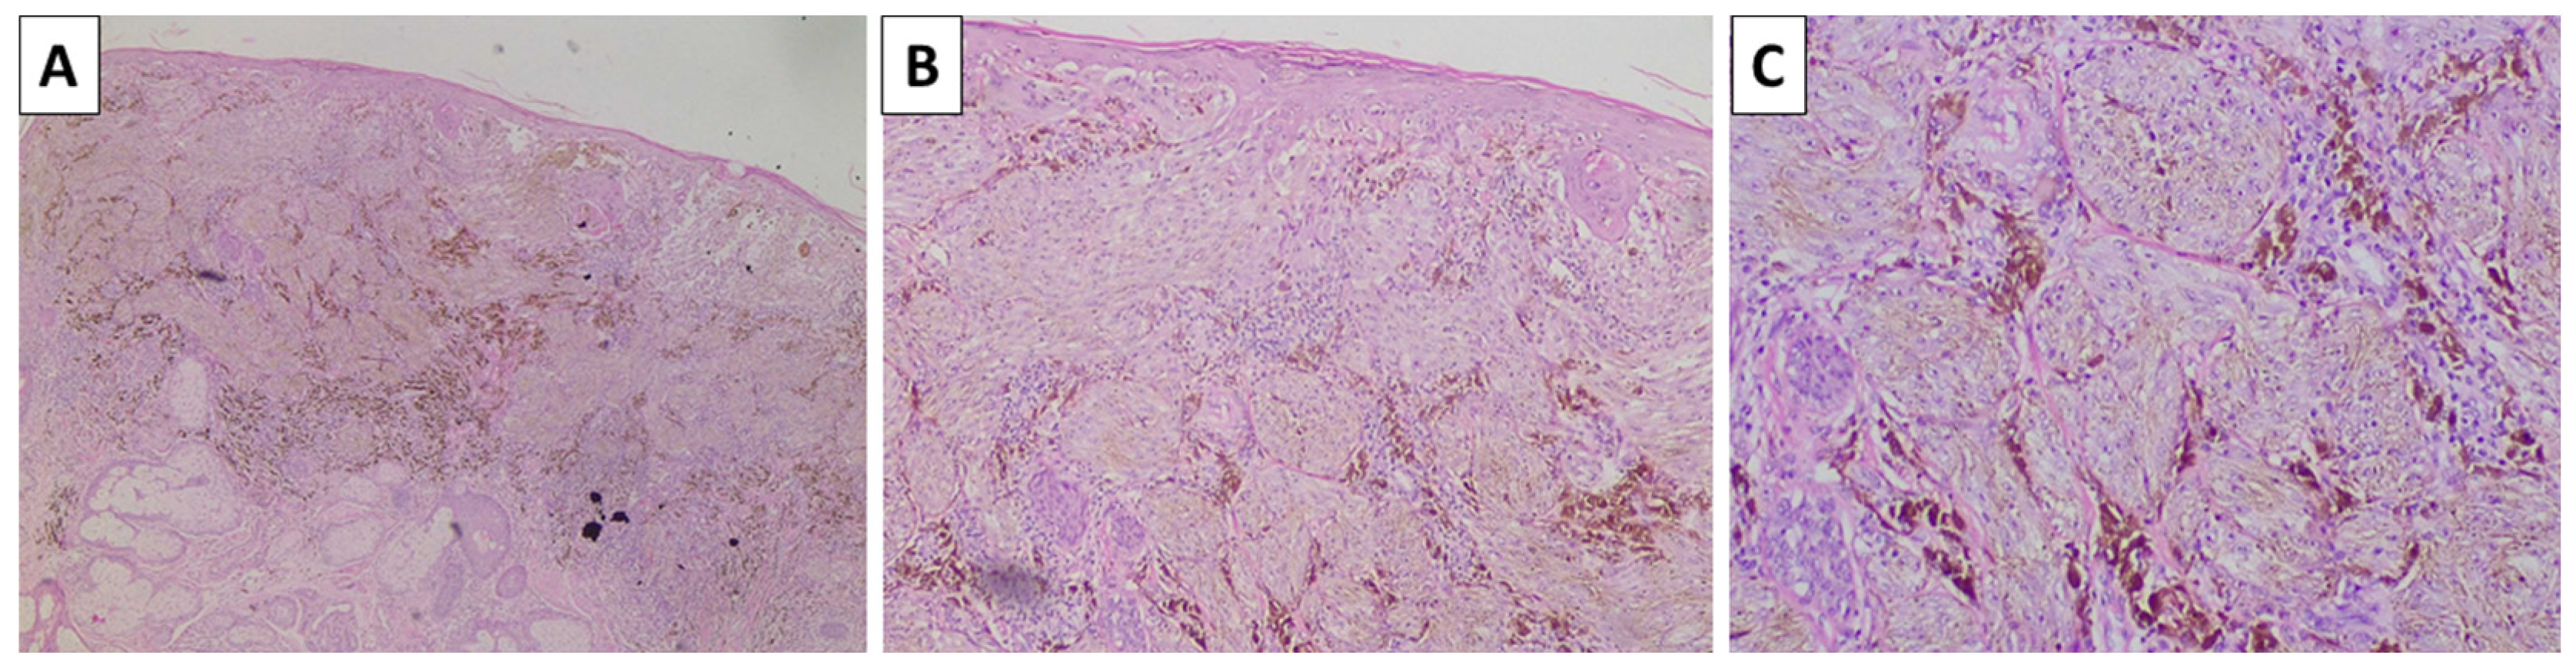

The lesion on the cheek, histologically, was represented by an atrophic epidermis and a melanocyte lesion with well-defined borders involving the epidermis and extending to the reticular dermis, composed of areas of marked pigmentation and cellularity, with oval to spindle-shaped cells with small monomorphic nuclei, speckled chromatin, and more abundant light or finely pigmented cytoplasm. The tumor cells are arranged in short fascicles and nests, surrounded by pigmented macrophages and circumscriptive sclerotic stroma. Hence, the lesion was diagnosed as a cellular blue nevus (Figure 4). The second lesion histologically was represented by an acanthotic lesion comprising large squamoid cells with light cytoplasm and easily identifiable mitoses, forming intraepidermal nests with microabscesses, single concentric keratin deposits, and focal ulceration. Hence, the lesion was diagnosed as a squamous cell carcinoma in situ (Figure 5). No basement membrane penetration was noted with a dense lichenoid infiltrate located under the lesion. The third lesion was histologically represented by a pigmented lesion with an asymmetric profile, comprising a dermally located neoplastic proliferation of epithelioid-type cells that progressed beyond the border of the dermal component, with nesting structures at the dermoepidermal junction and pagetoid spread. The tumor cells exhibited marked pleomorphism and eosinophilic cytoplasm, as well as vesicular nuclei and prominent nucleoli. An abundance of pigmented macrophages accompanied the sparse intervening stroma, and the pigmentation varied from apigmented to coarsely pigmented. No marked lymphocytic infiltrate, necrosis, or erosion of the surface epithelium was noted. However, the lesion extended to the reticular dermis (Clark IV) and had an overall thickness of 3 mm (Breslow stage III), without epidermal ulceration, the presence of vascular emboli, or atypical mitoses less than 5 per square millimeter (Figure 6). The neighboring pigmented lesion was represented by an epidermally based nevomelanocytic lesion comprising poorly pigmented cells and nests in the dermis, featuring nonpigmented nevomelanocytes with focal low-grade cytological atypia. Hence, the lesion was diagnosed as pT3a melanoma. The patient was referred to the oncology committee for treatment and is currently undergoing treatment and monitoring with stable disease and no progression of either the melanocytic or squamous cell neoplasia.

Figure 4.

Histopathology of the cheek lesion. (A) pigmented lesion in the superficial dermis, original magnification 40×; (B) higher magnification showing arrangement of the lesion in nests, original magnification 100×; (C) spindle cell melanocytes with subtle pigment deposition and a rim of sclerotic stroma surrounding the nests, original magnification 200×; staining (A–C) hematoxylin and eosin.